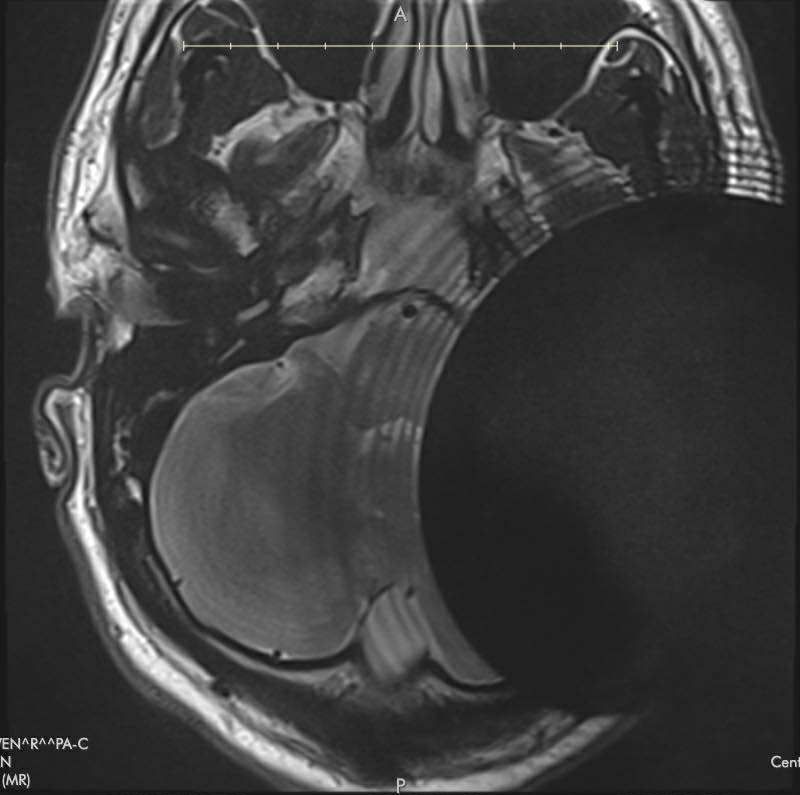

Recently, John reached out to me to share his story. John had lost hearing in one ear from an acoustic neuroma. He had chosen to get a Med-el Bonebridge implant bone anchored hearing device. His ENT doctor had told him it would cast a 17mm shadow for an MRI. However, he had a follow up MRI and it was useless for montioring his tumor. He then learned the literature from Med-el showed the shadow cast from a Bonebridge was 15cm. This is the MRI image he recieved.

He then proceeded to have a CT scan, which was not much better.